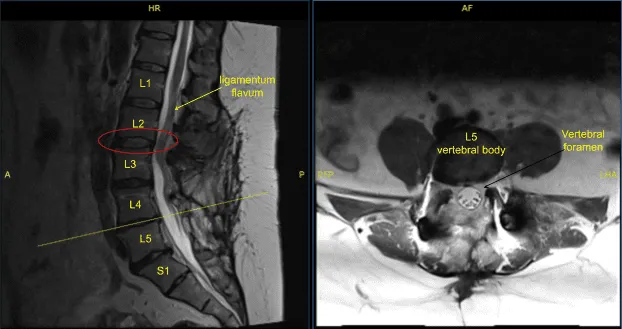

The patient was complaining of pain in both lower extremities. They had a history of L3 to S1 fusion done by another physician. Imaging studies showed good fusion mass from L3 to S1 but compression over L2-L3 segment with bilateral neural foraminal compression of L3 along with bony island formation over L3-L4 region with foraminal compression.

Disc bulge, facet osteoarthritis, buckling of ligamentum flavum